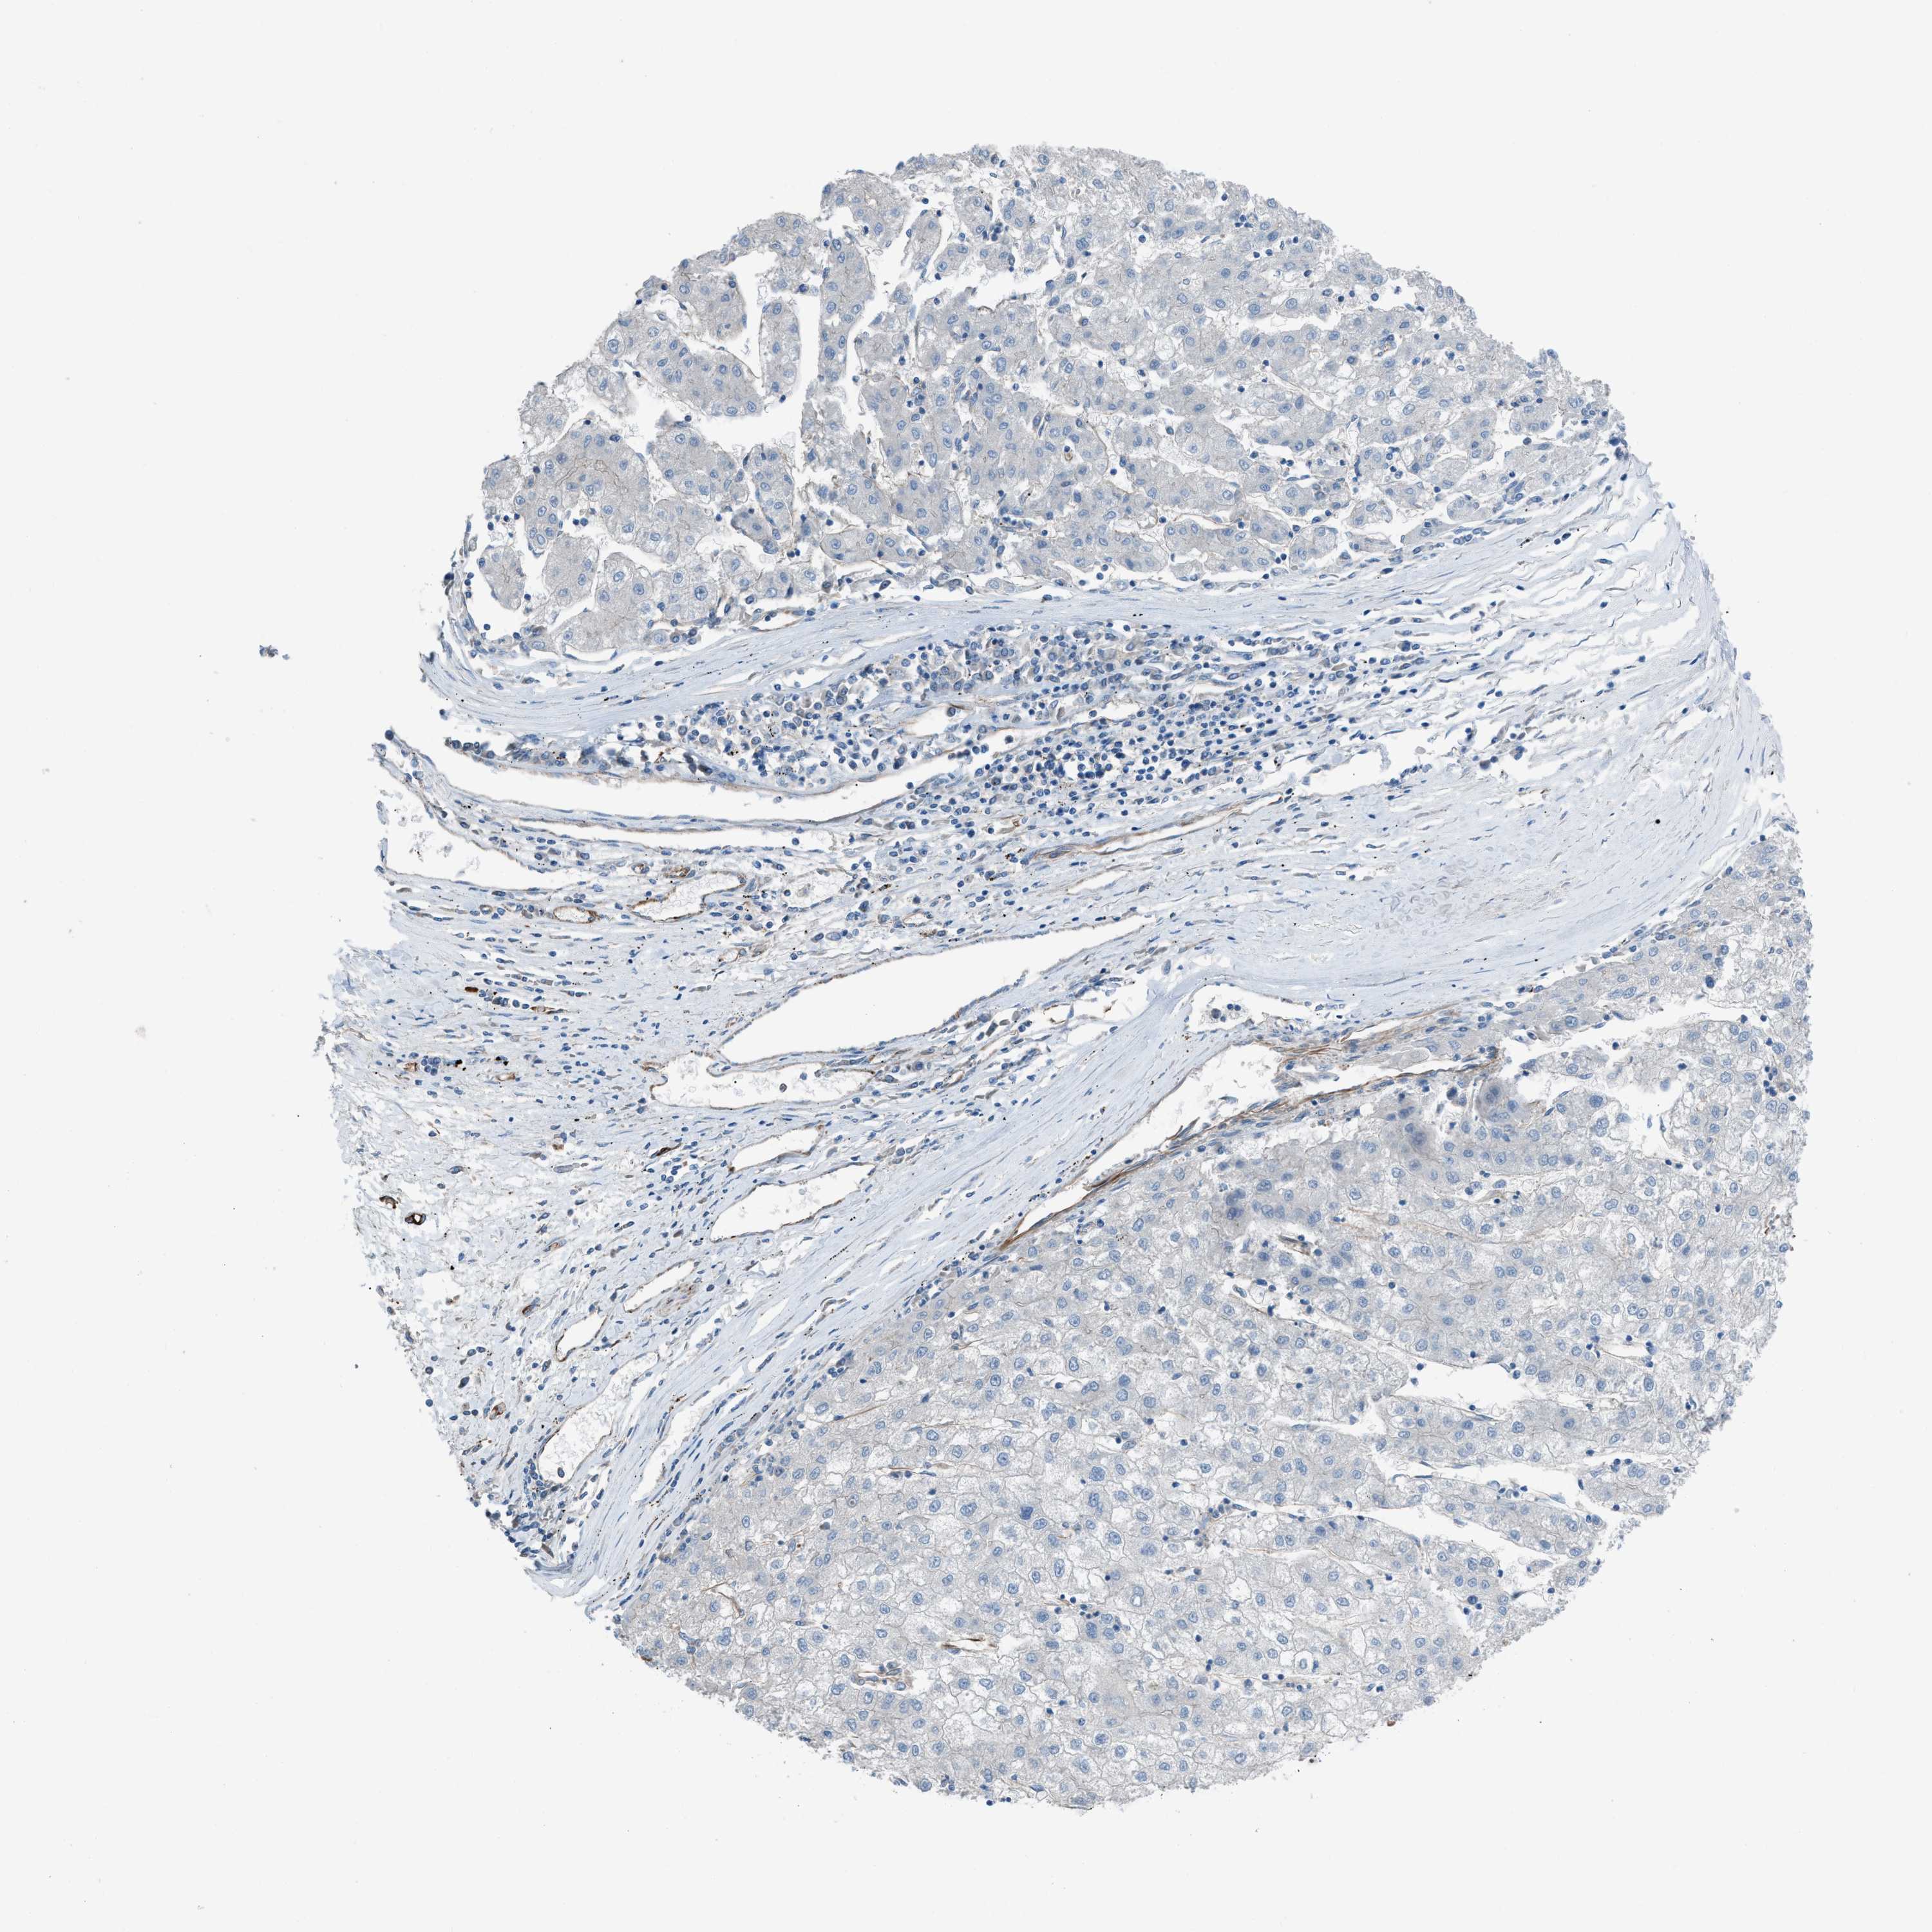

LIVER CANCER - Protein expressioni

A mouse-over function shows sample information and annotation data. Click on an image to view it in a full screen mode. Samples can be filtered based on level of antibody staining by selecting one or several of the following categories: high, medium, low and not detected. The assay and annotation is described here.

Note that samples used for immunohistochemistry by the Human Protein Atlas do not correspond to samples in the TCGA dataset.

Antibody stainingi

Antibody staining in the annotated cell types in the current human tissue is reported as not detected, low, medium, or high, based on conventional immunohistochemistry profiling in selected tissues. This score is based on the combination of the staining intensity and fraction of stained cells.

Each image is clickable and will lead to virtual microscopy that enables deeper exploration of all samples and also displays staining intensity scores, fraction scores and subcellular localization as well as patient and tissue information for each sample.

Antibody HPA016439

Staining

High

Medium

Low

Not detected

Intensity

Strong

Moderate

Weak

Negative

Quantity

>75%

75%-25%

<25%

None

Location

Nuclear

Cytoplasmic/membranous

Cytoplasmic/membranous,nuclear

Cholangiocarcinoma

Carcinoma, Hepatocellular, NOS